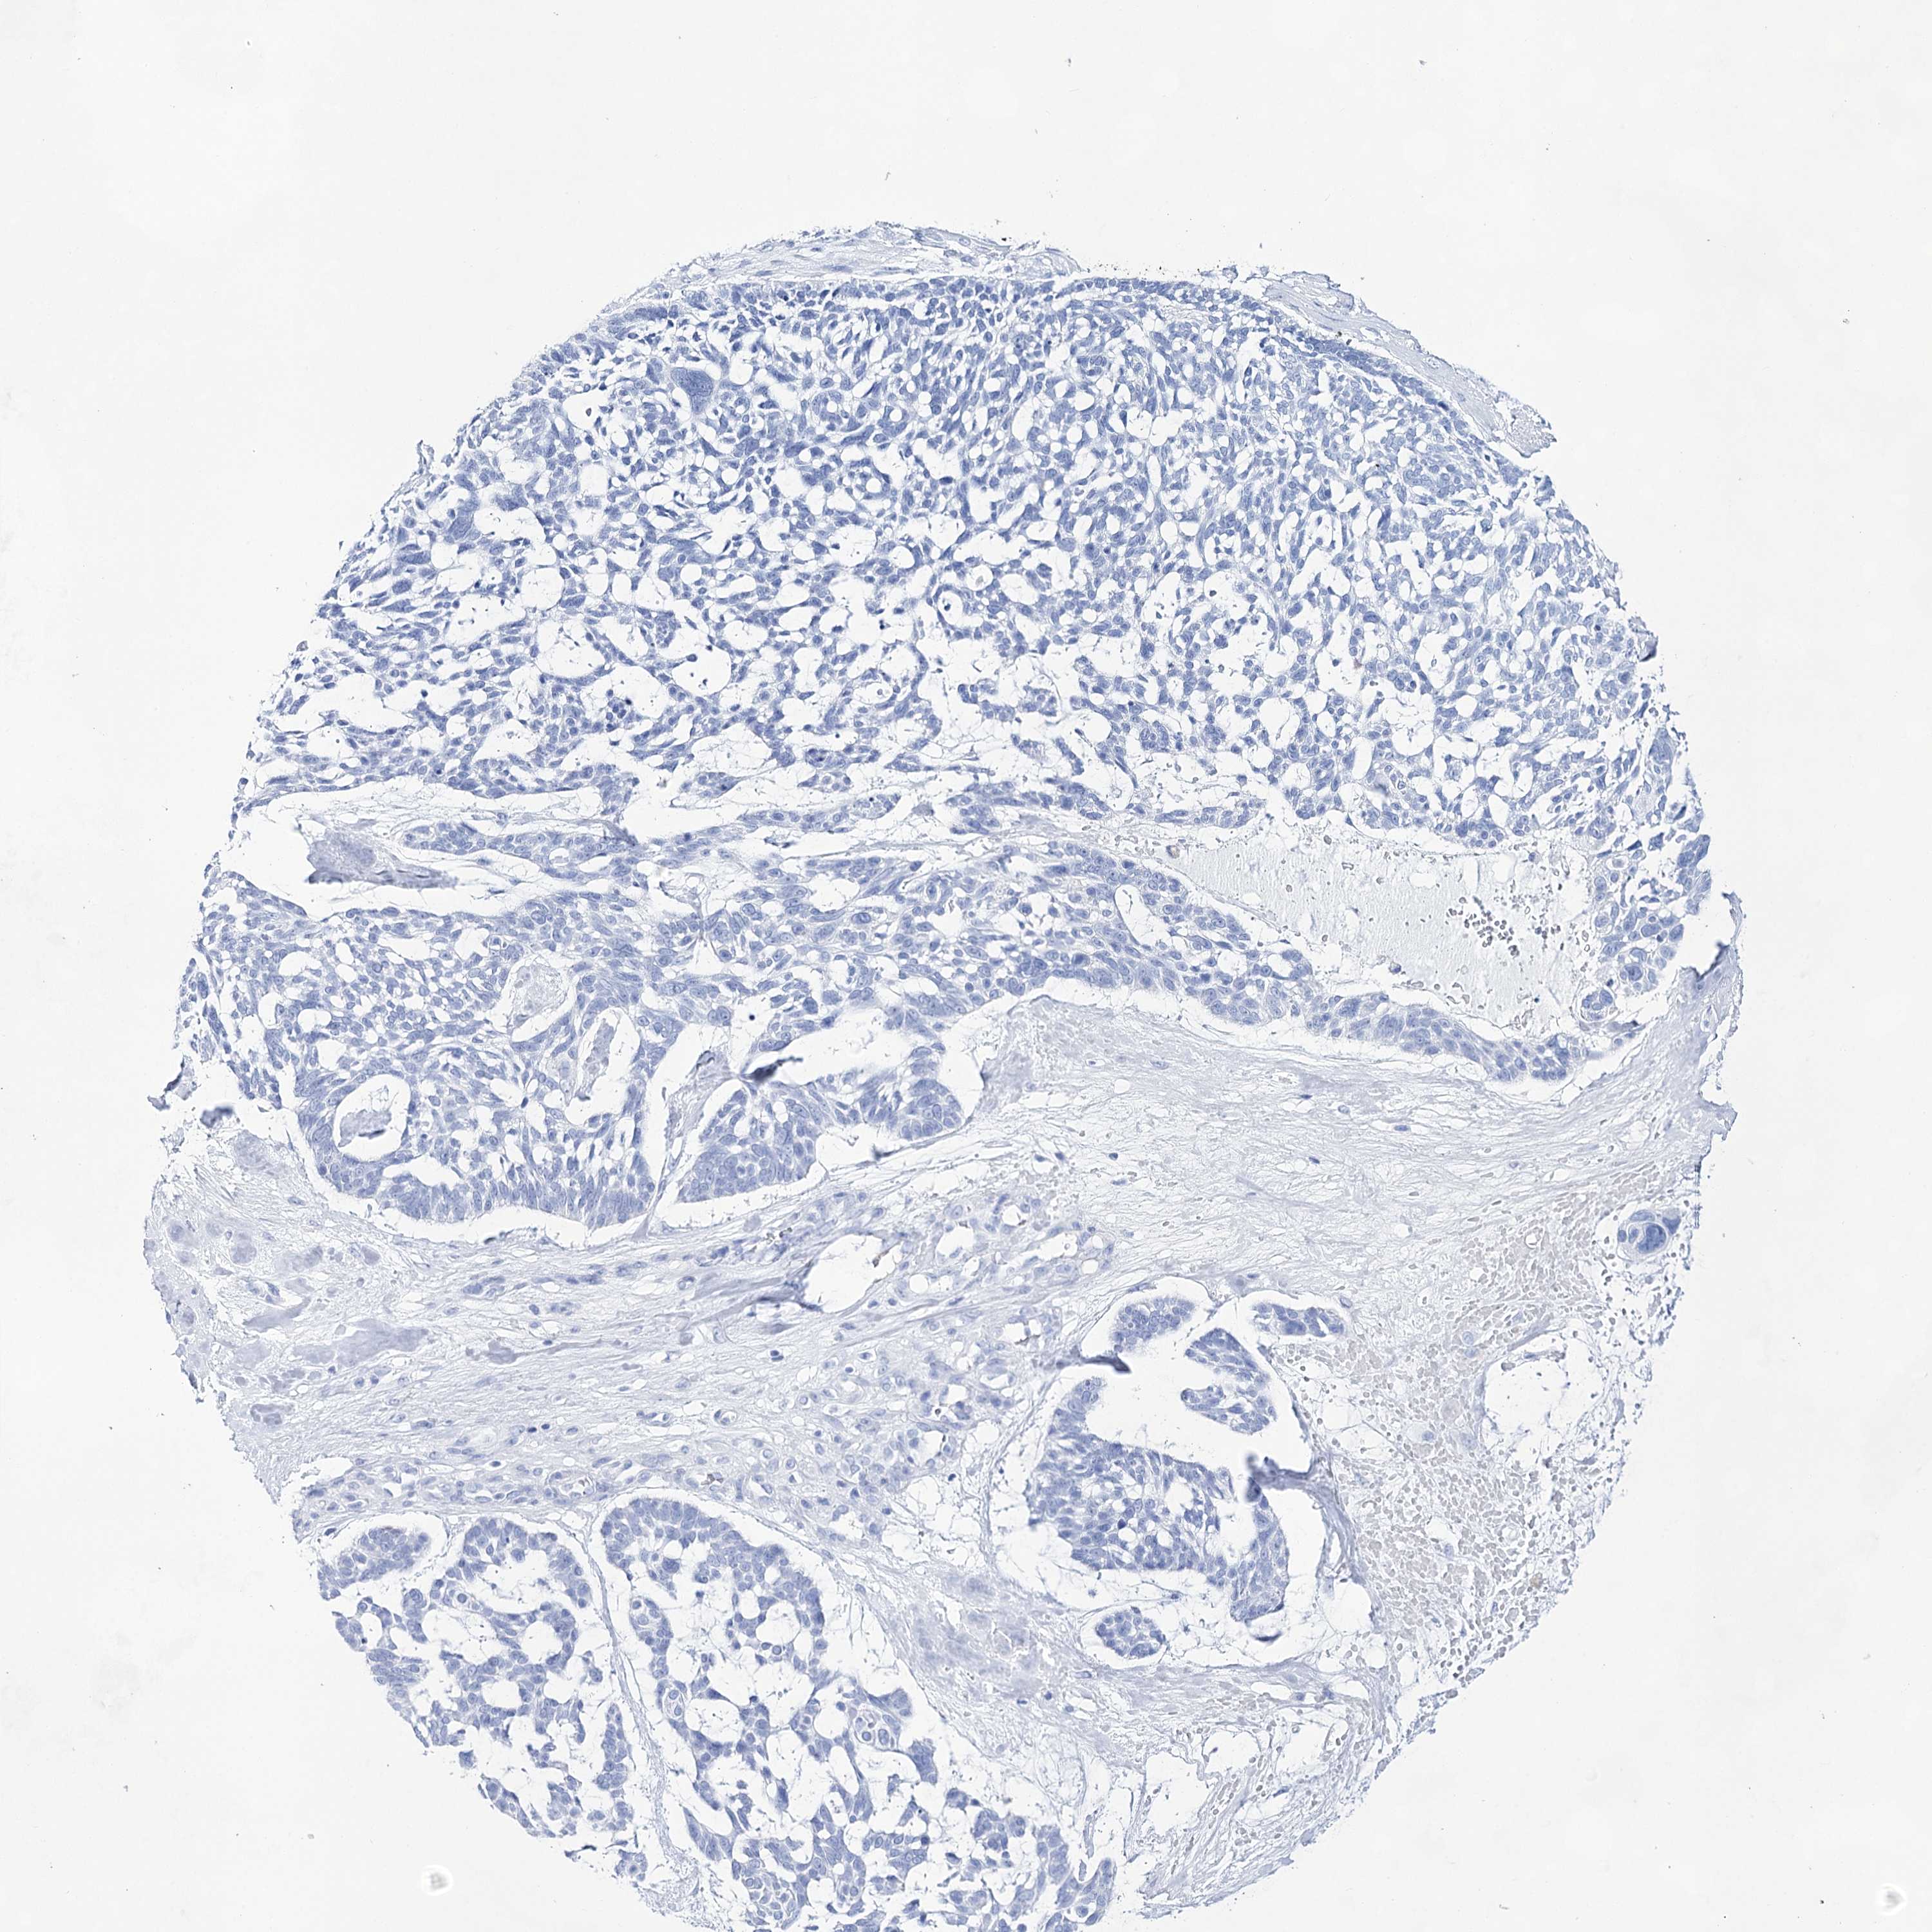

CANCER SKIN CANCER Show tissue menu

Basal cell and squamous cell cancer

SKIN CANCER - Protein expressioni

A mouse-over function shows sample information and annotation data. Click on an image to view it in a full screen mode. Samples can be filtered based on level of antibody staining by selecting one or several of the following categories: high, medium, low and not detected. The assay and annotation is described here.

Each image is clickable and will lead to virtual microscopy that enables deeper exploration of all samples and also displays staining intensity scores, fraction scores and subcellular localization as well as patient and tissue information for each sample.

Antibody HPA029855

Antibody HPA029856

Antibody CAB026343

Basal cell carcinoma

Squamous cell carcinoma, NOS

Squamous cell carcinoma, metastatic, NOS